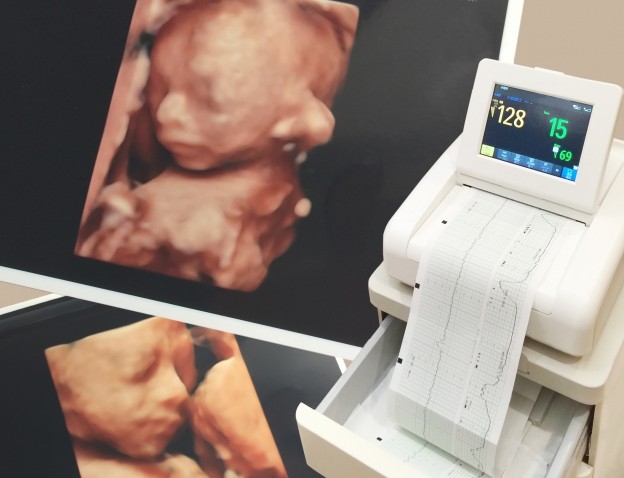

現在は三次元測定(3D)のエコーで胎児の表情も分かるようになり、どんな顔つきかをしてるのか?も分かるようになってるよ。

俺も妻のお腹の中にいる娘の表情まで把握できてるから、どんな顔してるのかってのも事前に知る事ができて便利だと感じた。

さらにこっちは3D撮影した結構リアルなエコー写真ね。

かなり顔の形がハッキリ見えるから、どんな顔してるのか?も分かりやすいよね。

しかも、この時点で顔を見て二重瞼だという事も分かるくらい明確な映像として確認できちゃうわけ。

俺は二重瞼で妻は一重瞼なんだけど、正直言って俺の二重を継いでほしかったから凄く嬉しかったよ。